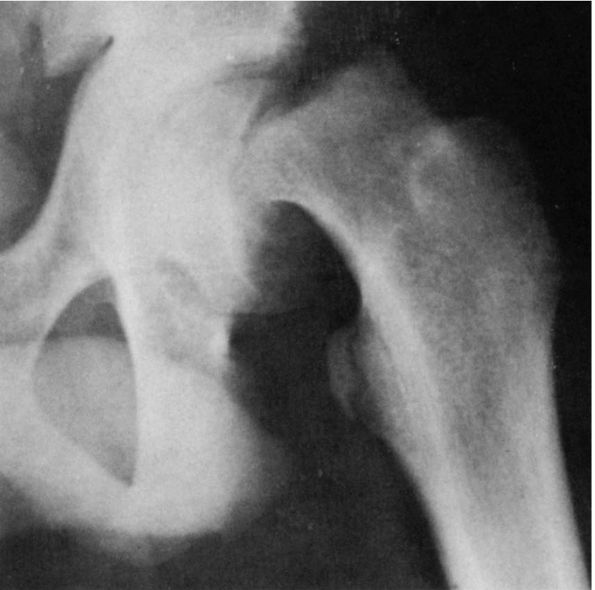

FIGURE 15-5.

Untreated right congenital hip dysplasia in an adult. Note the lack of development of acetabular shape and depth. No secondary acetabulum exists. The left hip is normal. |

is important to appreciate that the normal concave shape of the

acetabulum develops in response to the presence of a spherical femoral

head. Experimental studies in animals as well as observations in humans

with unreduced congenital hip dislocations show that the acetabulum

does not develop its normal concave shape. Instead, with a complete

dislocation, the triradiate cartilage grows normally, and hence the

innominate bone reaches its normal length (Figure 15-5);

but the acetabular cartilage atrophies and degenerates, and the

acetabulum appears flattened. The depth of the acetabulum increases